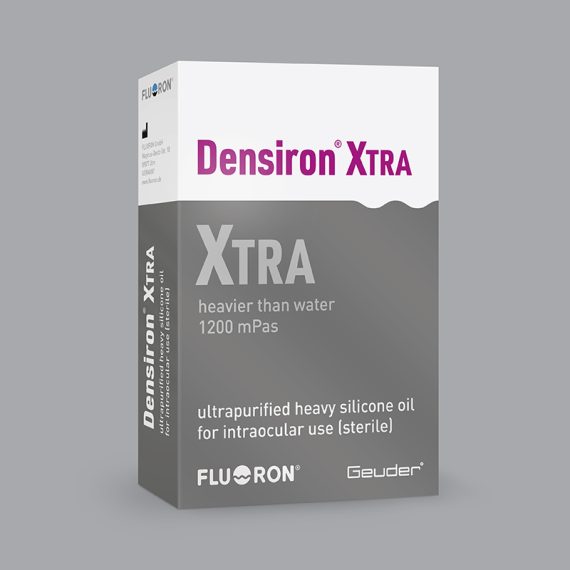

Fluoron Densiron XTRA®Fluoron's Densiron XTRA® is a next-generation heavy silicone oil...Code: G-80910, G-80920, G-80925Explore

Fluoron Densiron XTRA®Fluoron's Densiron XTRA® is a next-generation heavy silicone oil...Code: G-80910, G-80920, G-80925Explore -